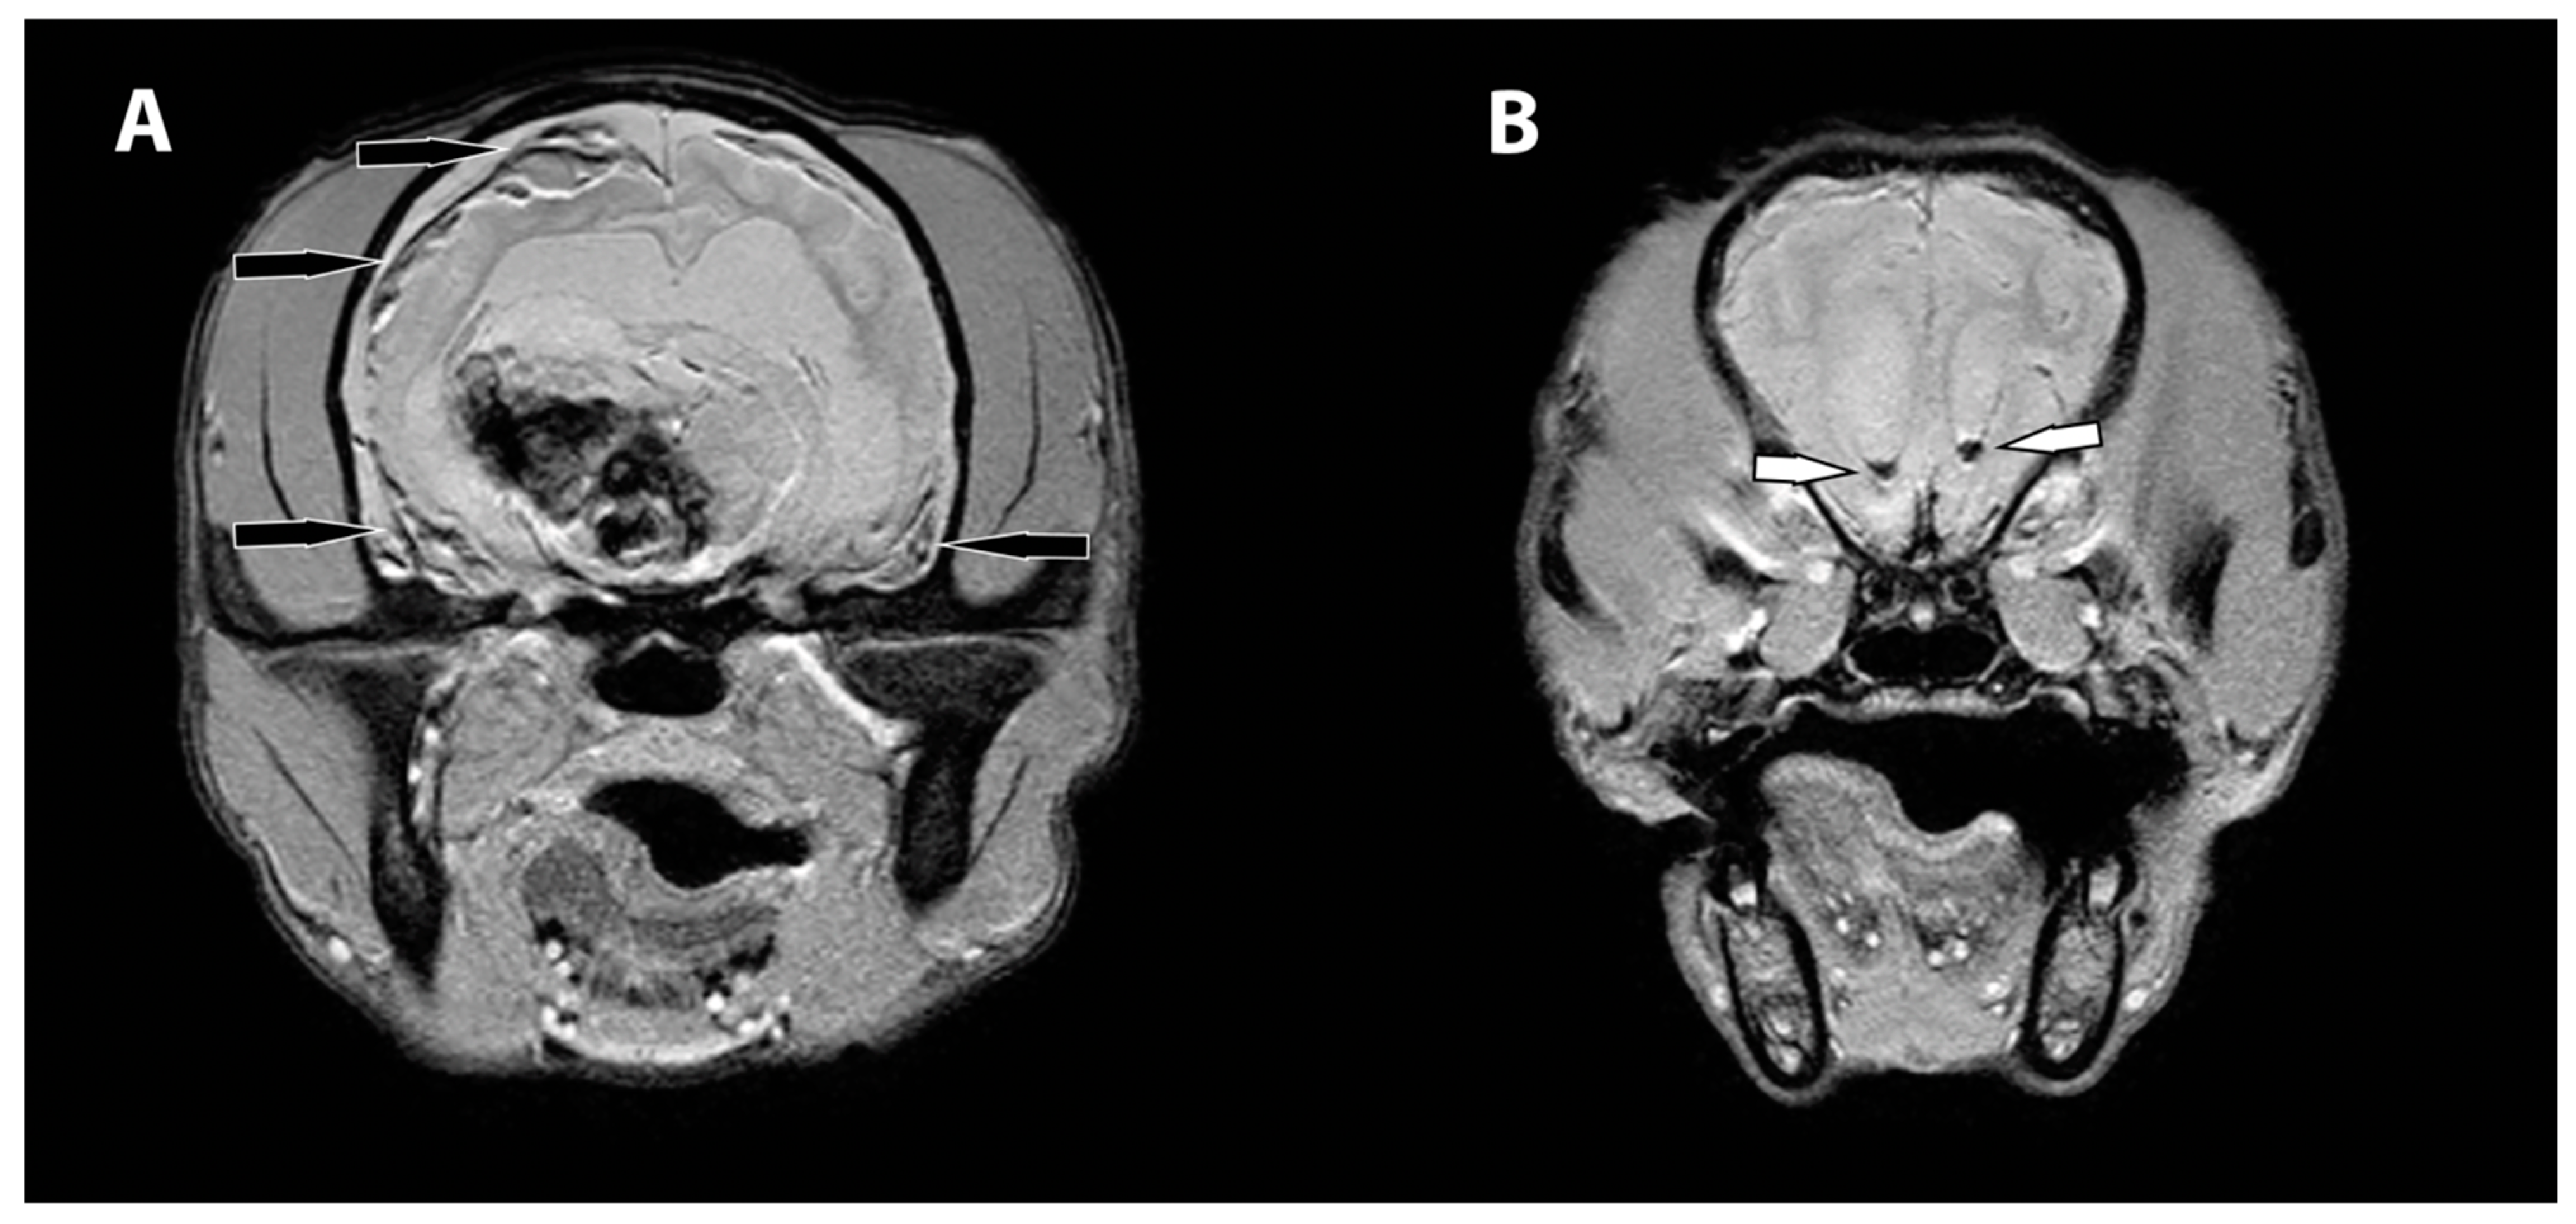

- Young, B.D.; Levine, J.M.; Porter, B.F.; Chen-Allen, A.V.; Rossmeisl, J.H.; Platt, S.R.; Kent, M.; Fosgate, G.T.; Schatzberg, S.J. Magnetic resonance imaging features of intracranial astrocytomas and oligodendrogliomas in dogs. Vet. Radiol. Ultrasound 2011, 52, 132–141. [Google Scholar] [CrossRef]

- Lee, Y.Y.; Van Tassel, P.; Bruner, J.M.; Moser, R.P.; Share, J.C. Juvenile pilocytic astrocytomas: CT and MR characteristics. AJR Am. J. Roentgenol. 1989, 152, 1263–1270. [Google Scholar] [CrossRef] [Green Version]

- Kumar, A.J.; Leeds, N.E.; Kumar, V.A.; Fuller, G.N.; Lang, F.F.; Milas, Z.; Weinberg, J.S.; Ater, J.L.; Sawaya, R. Magnetic resonance imaging features of pilocytic astrocytoma of the brain mimicking high-grade gliomas. J. Comput. Assist. Tomogr. 2010, 34, 601–611. [Google Scholar] [CrossRef]

- Nakano, Y.; Yamamoto, J.; Takahashi, M.; Soejima, Y.; Akiba, D.; Kitagawa, T.; Ueta, K.; Miyaoka, R.; Umemura, T.; Nishizawa, S. Pilocytic astrocytoma presenting with atypical features on magnetic resonance imaging. J. Neuroradiol. 2015, 42, 278–282. [Google Scholar] [CrossRef] [PubMed]